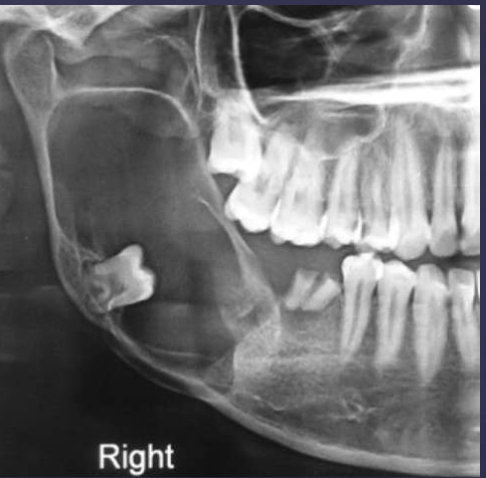

describe the ameloblastoma in this radiograph

multilocular w/ coarse septae

thinning of inferior mand border

displacement of teeth + IAN